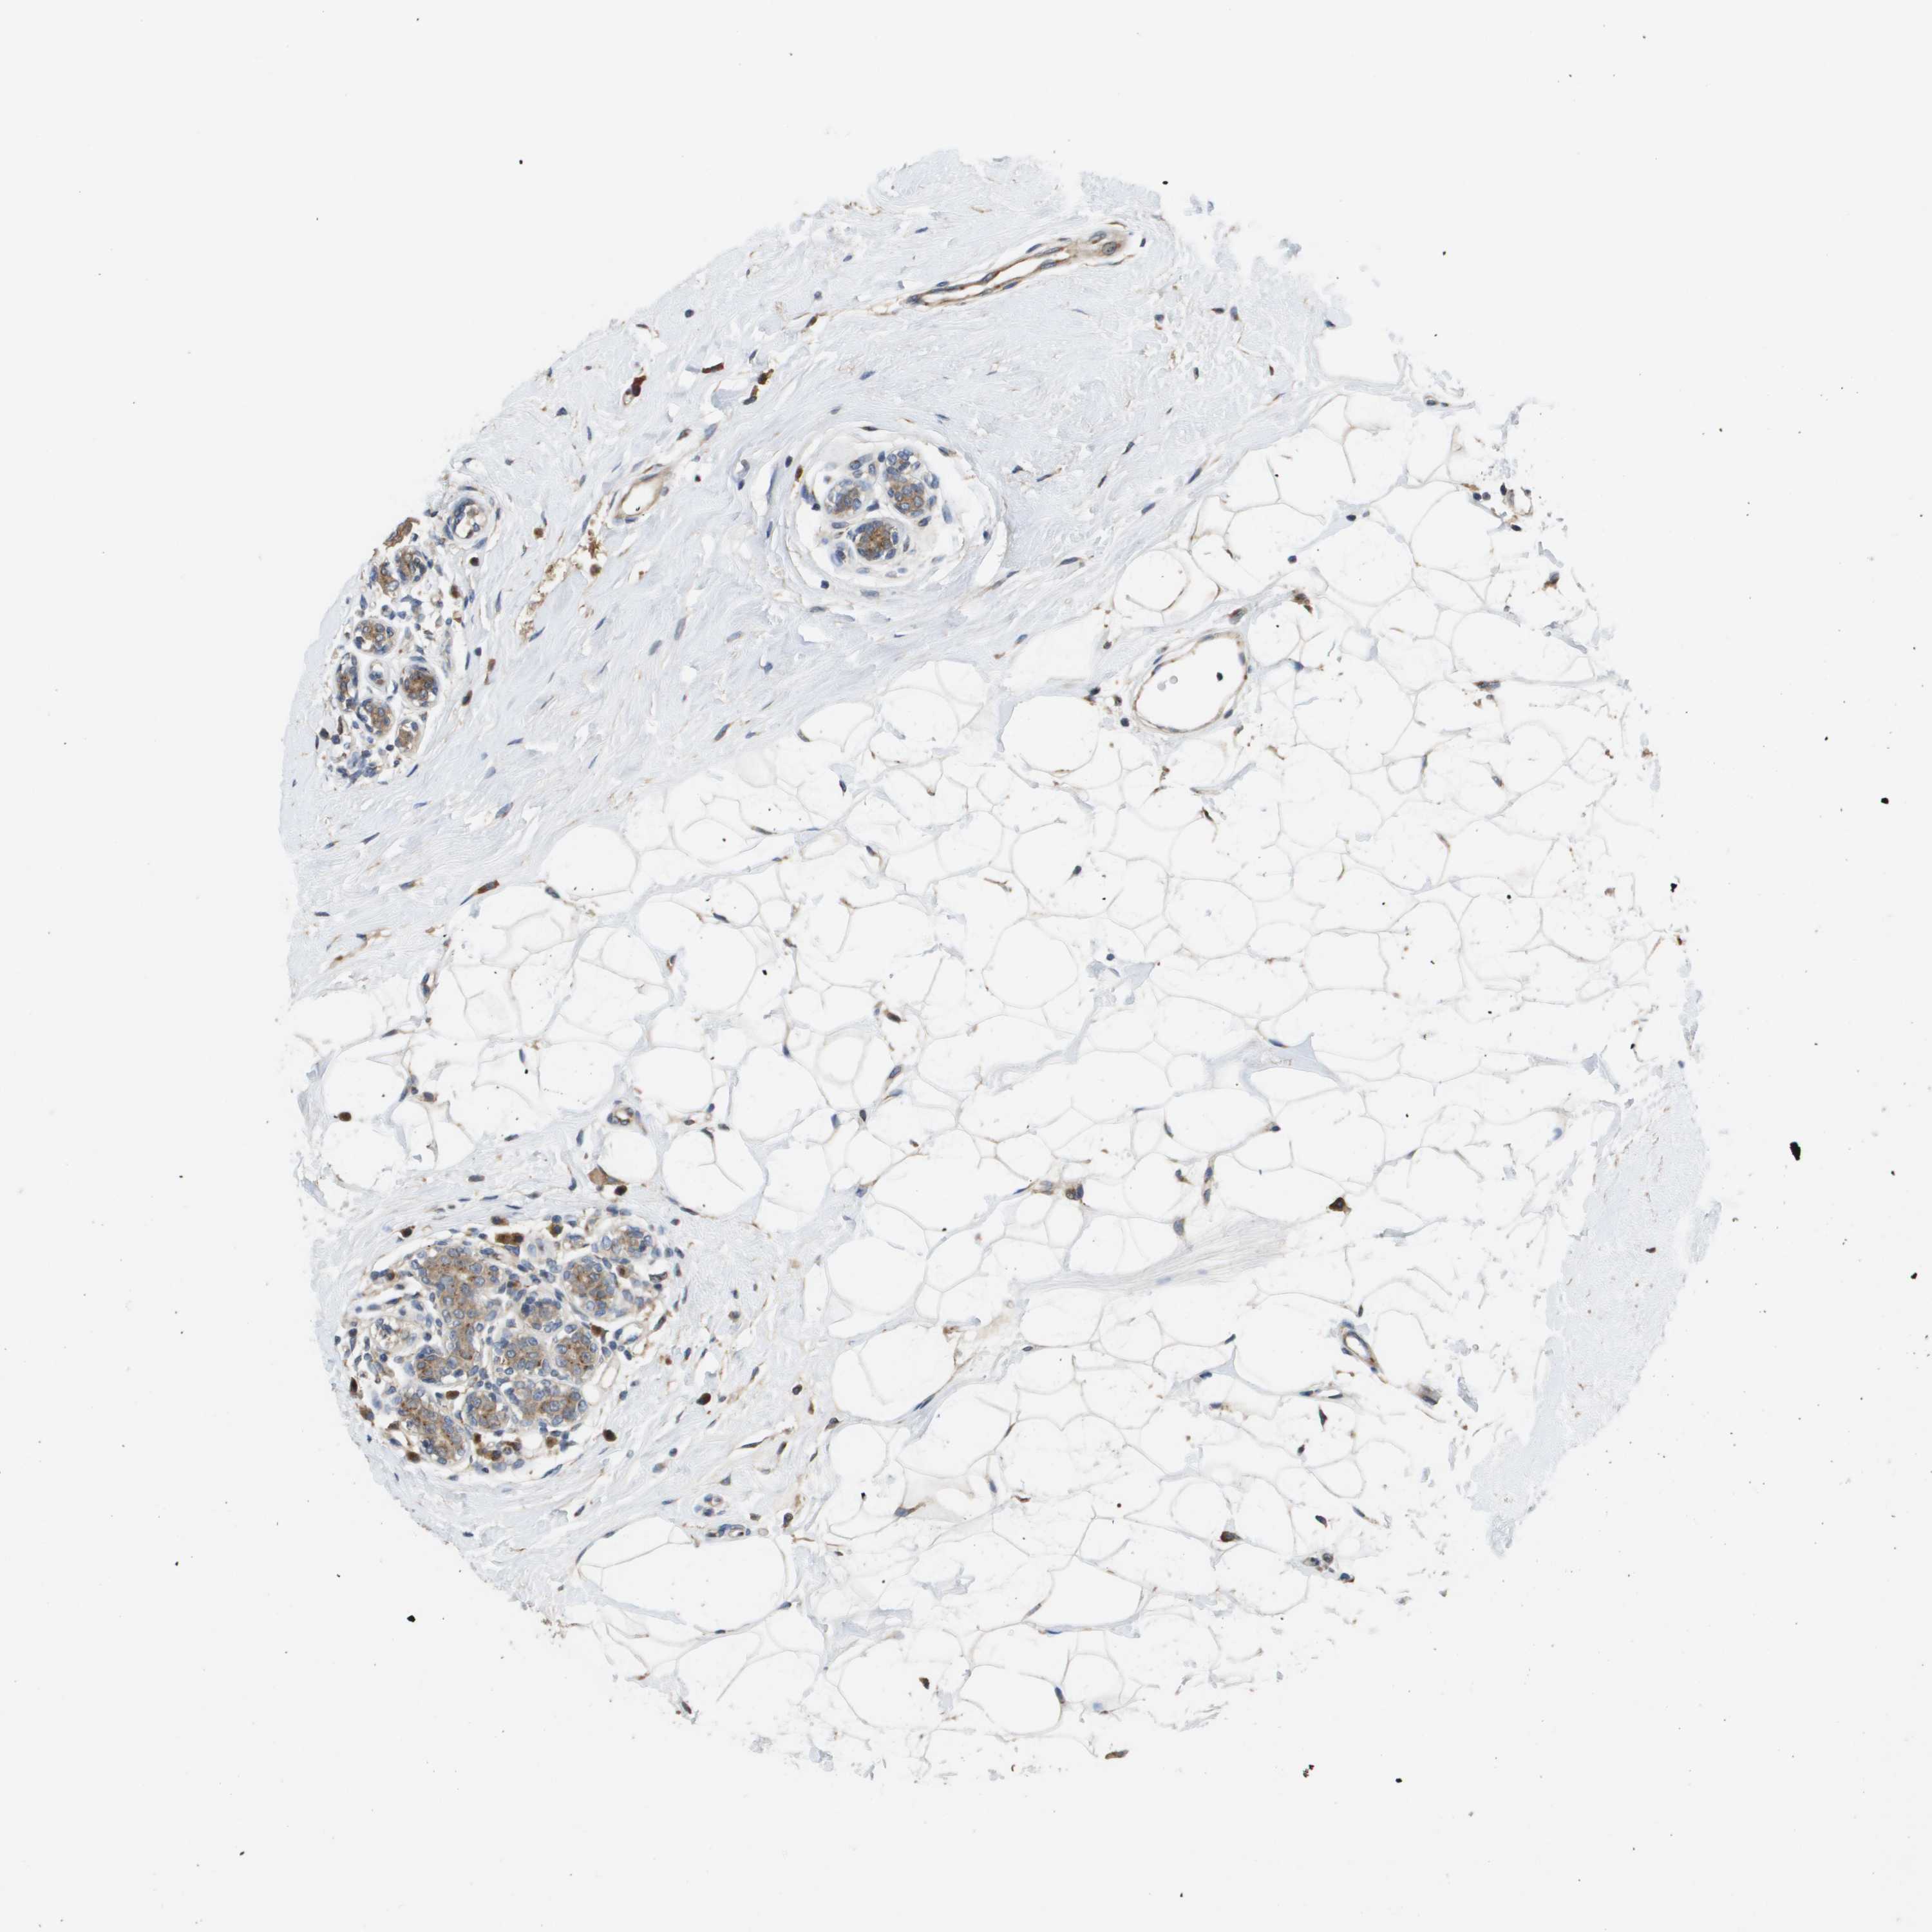

CANCER BREAST CANCER Show tissue menu

BRCA TCGA BRCA VALIDATION PROTEIN EXPRESSION